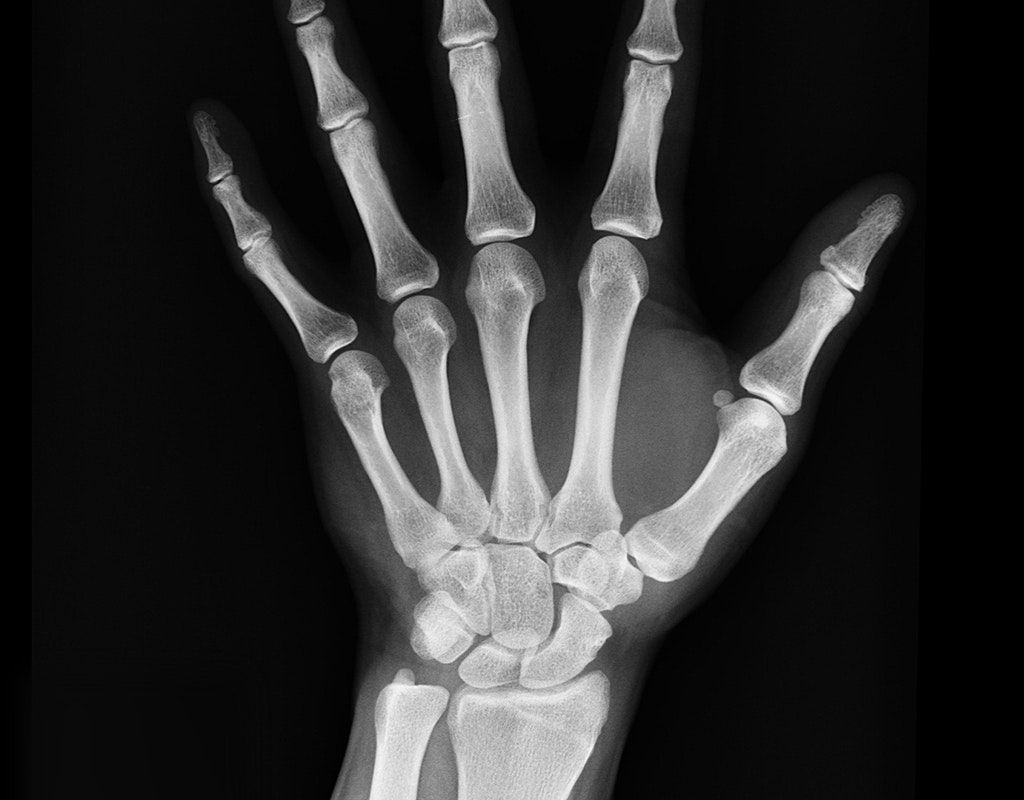

Modern healthcare facilities rely heavily on medical imaging technologies like X-rays, MRIs, and CT scans for accurate diagnoses.

Modern AI systems can now analyze medical images with unprecedented precision, helping radiologists identify subtle abnormalities that might otherwise go unnoticed.